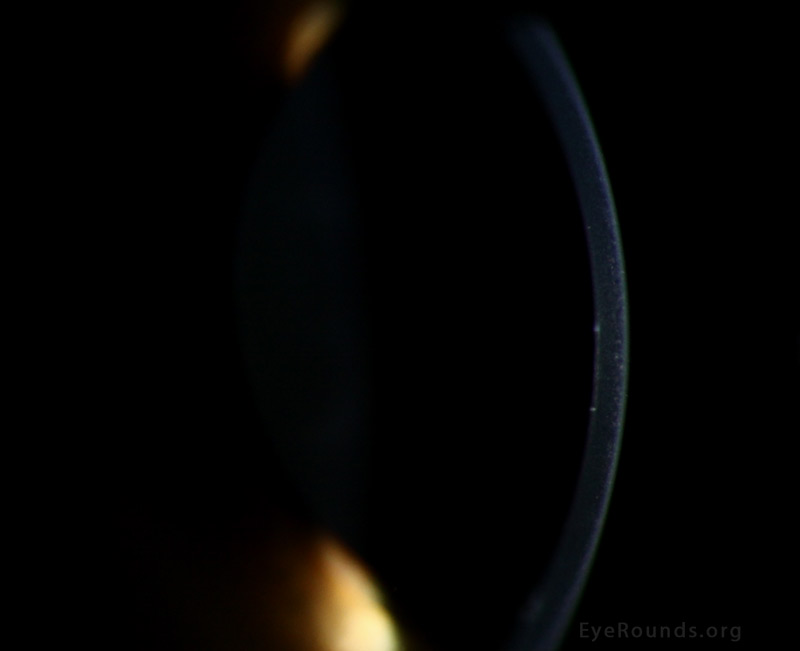

From webeye.ophth.uiowa.edu

Posterior Polymorphous Corneal Dystrophy (PPMD) Snail Tracks In Eyes snail track degeneration is a glistening white frost like area, elongated oval or spindle shaped and has multiple white dots within it. peripheral retinal degeneration (prd) is a broad term which includes various lesions such as the lattice degeneration,. snail track degeneration : They are typically bilateral, in the superotemporal quadrant, and more commonly seen in myopic. Snail Tracks In Eyes.

Atlas Entry Posterior Polymorphous Corneal Dystrophy (PPMD) Snail Tracks In Eyes They are seen in the temporal quadrant and the majority are seen at least 2dd anterior to the equator. snail track degeneration : band lesions, sometimes called snail tracks, are classically horizontal lesions with parallel, scalloped, non. They are typically bilateral, in the superotemporal quadrant, and more commonly seen in myopic patients. snail track degeneration is a. Snail Tracks In Eyes.

Atlas Entry Posterior Polymorphous Corneal Dystrophy (PPMD) Snail Tracks In Eyes snail track degeneration is a glistening white frost like area, elongated oval or spindle shaped and has multiple white dots within it. They are seen in the temporal quadrant and the majority are seen at least 2dd anterior to the equator. peripheral retinal degeneration (prd) is a broad term which includes various lesions such as the lattice degeneration,.. Snail Tracks In Eyes.

Atlas Entry Posterior Polymorphous Corneal Dystrophy (PPMD) Snail Tracks In Eyes snail track degenerations are sharply demarcated, elongated groups of white dots in the far periphery. snail track degeneration : peripheral retinal degeneration (prd) is a broad term which includes various lesions such as the lattice degeneration,. They are seen in the temporal quadrant and the majority are seen at least 2dd anterior to the equator. snail. Snail Tracks In Eyes.

Posterior Polymorphous Corneal Dystrophy (PPMD) Snail Tracks In Eyes They are typically bilateral, in the superotemporal quadrant, and more commonly seen in myopic patients. snail track degenerations are sharply demarcated, elongated groups of white dots in the far periphery. peripheral retinal degeneration (prd) is a broad term which includes various lesions such as the lattice degeneration,. They are seen in the temporal quadrant and the majority are. Snail Tracks In Eyes.

Posterior Polymorphous Corneal Dystrophy (PPMD) Snail Tracks In Eyes snail track degeneration : peripheral retinal degeneration (prd) is a broad term which includes various lesions such as the lattice degeneration,. They are typically bilateral, in the superotemporal quadrant, and more commonly seen in myopic patients. snail track degeneration is a glistening white frost like area, elongated oval or spindle shaped and has multiple white dots within. Snail Tracks In Eyes.